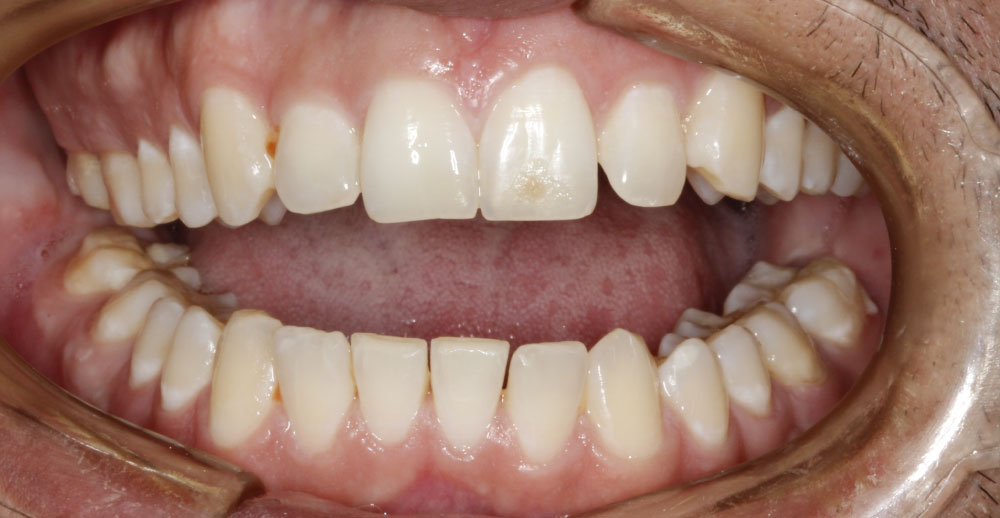

A 25-year-old male patient sought the Oral-Maxillofacial Surgery and Traumatology service at the "Dr. Mario Gatti" Municipal Hospital (Campinas-SP) in January 2016, with complaint of limitation of progressive mouth opening (2 mm), seven months after extraction of upper and lower third molars (Figure 1 and Figure 2). The patient denied prior medical problems, prior episodes of heterotopic ossification in other locations, history of family diseases and did not present hallux valgus. The hypothesis of MOP was ruled out by previous genetic test (ACVR1 gene). The patient reported using a single dose of bisphosphonate (Zolendroic Acid) and was taking Vitamin C and Indomethacin after the appearance of symptoms, a medication that had been prescribed in another service for one month.

Figure 1: Extraoral photography evidencing severe trismus. View Figure 1

Figure 2: A) Intraoral photography showing maximum intercuspation; B) Intraoral photography showing maximum mouth opening. View Figure 2